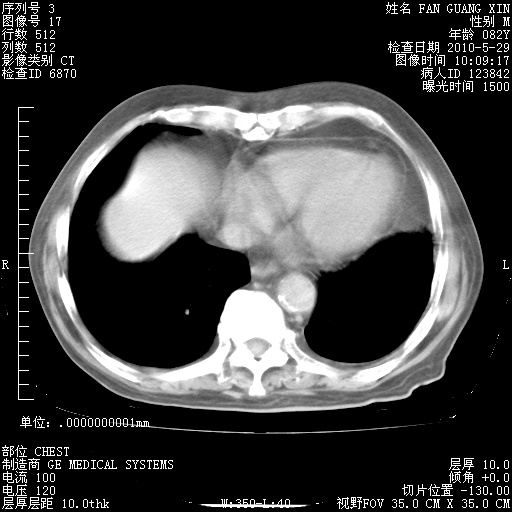

再治疗10天后的肺部CT 纵膈窗

阅读此次胸部CT,肺间质渗出性改变较入院时有吸收。目前从体温、白细胞、中性分叶明显增高,肯定存在细菌感染(发生医院感染哦,若无消化道及泌尿系统等感染的依据,肺部感染可能大)。若你院头孢哌酮舒巴坦钠耐药率较高,同意你的方案,若48小时体温仍高,可考虑使用碳青霉稀类抗菌药物,同时可予超声雾化、注意滴数时加大液体量。白蛋白33.30g/L较低哦,需加强营养等支持治疗。